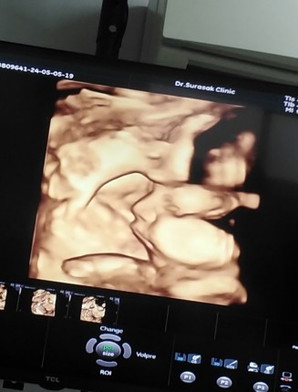

ไหนแม่ๆบ้านไหนไปซาวด์4มิติมาบ้างคะ น้องยอมให้เห็นหน้ามั้ยคะ บ้านนี้น้องกำหนดคลอดเดือนกรกฎาคม หาทีมกรกฎาจ้าาาา

กำหนดคลอด19ก.ค ค่ะ น้องไม่ยอมให้เห็นหน้าเห็นแต่ข้างๆ หมอกระตุ้นก็ไม่ตื่นหลับลึก555 หมอบอกลูกขี้เกียจ แต่ยังอยู่ท่าขวางอยู่เลยคะ

#ทีมเดียวกันจ้า ไปมาแร้วเหมือนกัน น้องเหมือนจะไม่ยอม เอามือบังหน้าตลอด เขย่าๆยุหลายครั้งเหมือนกันคะ 🤣

กำหนดคลอด20 กรกฎาคมเหมือนกันน้องให้เห้นทุกรอบเลย☺️☺️